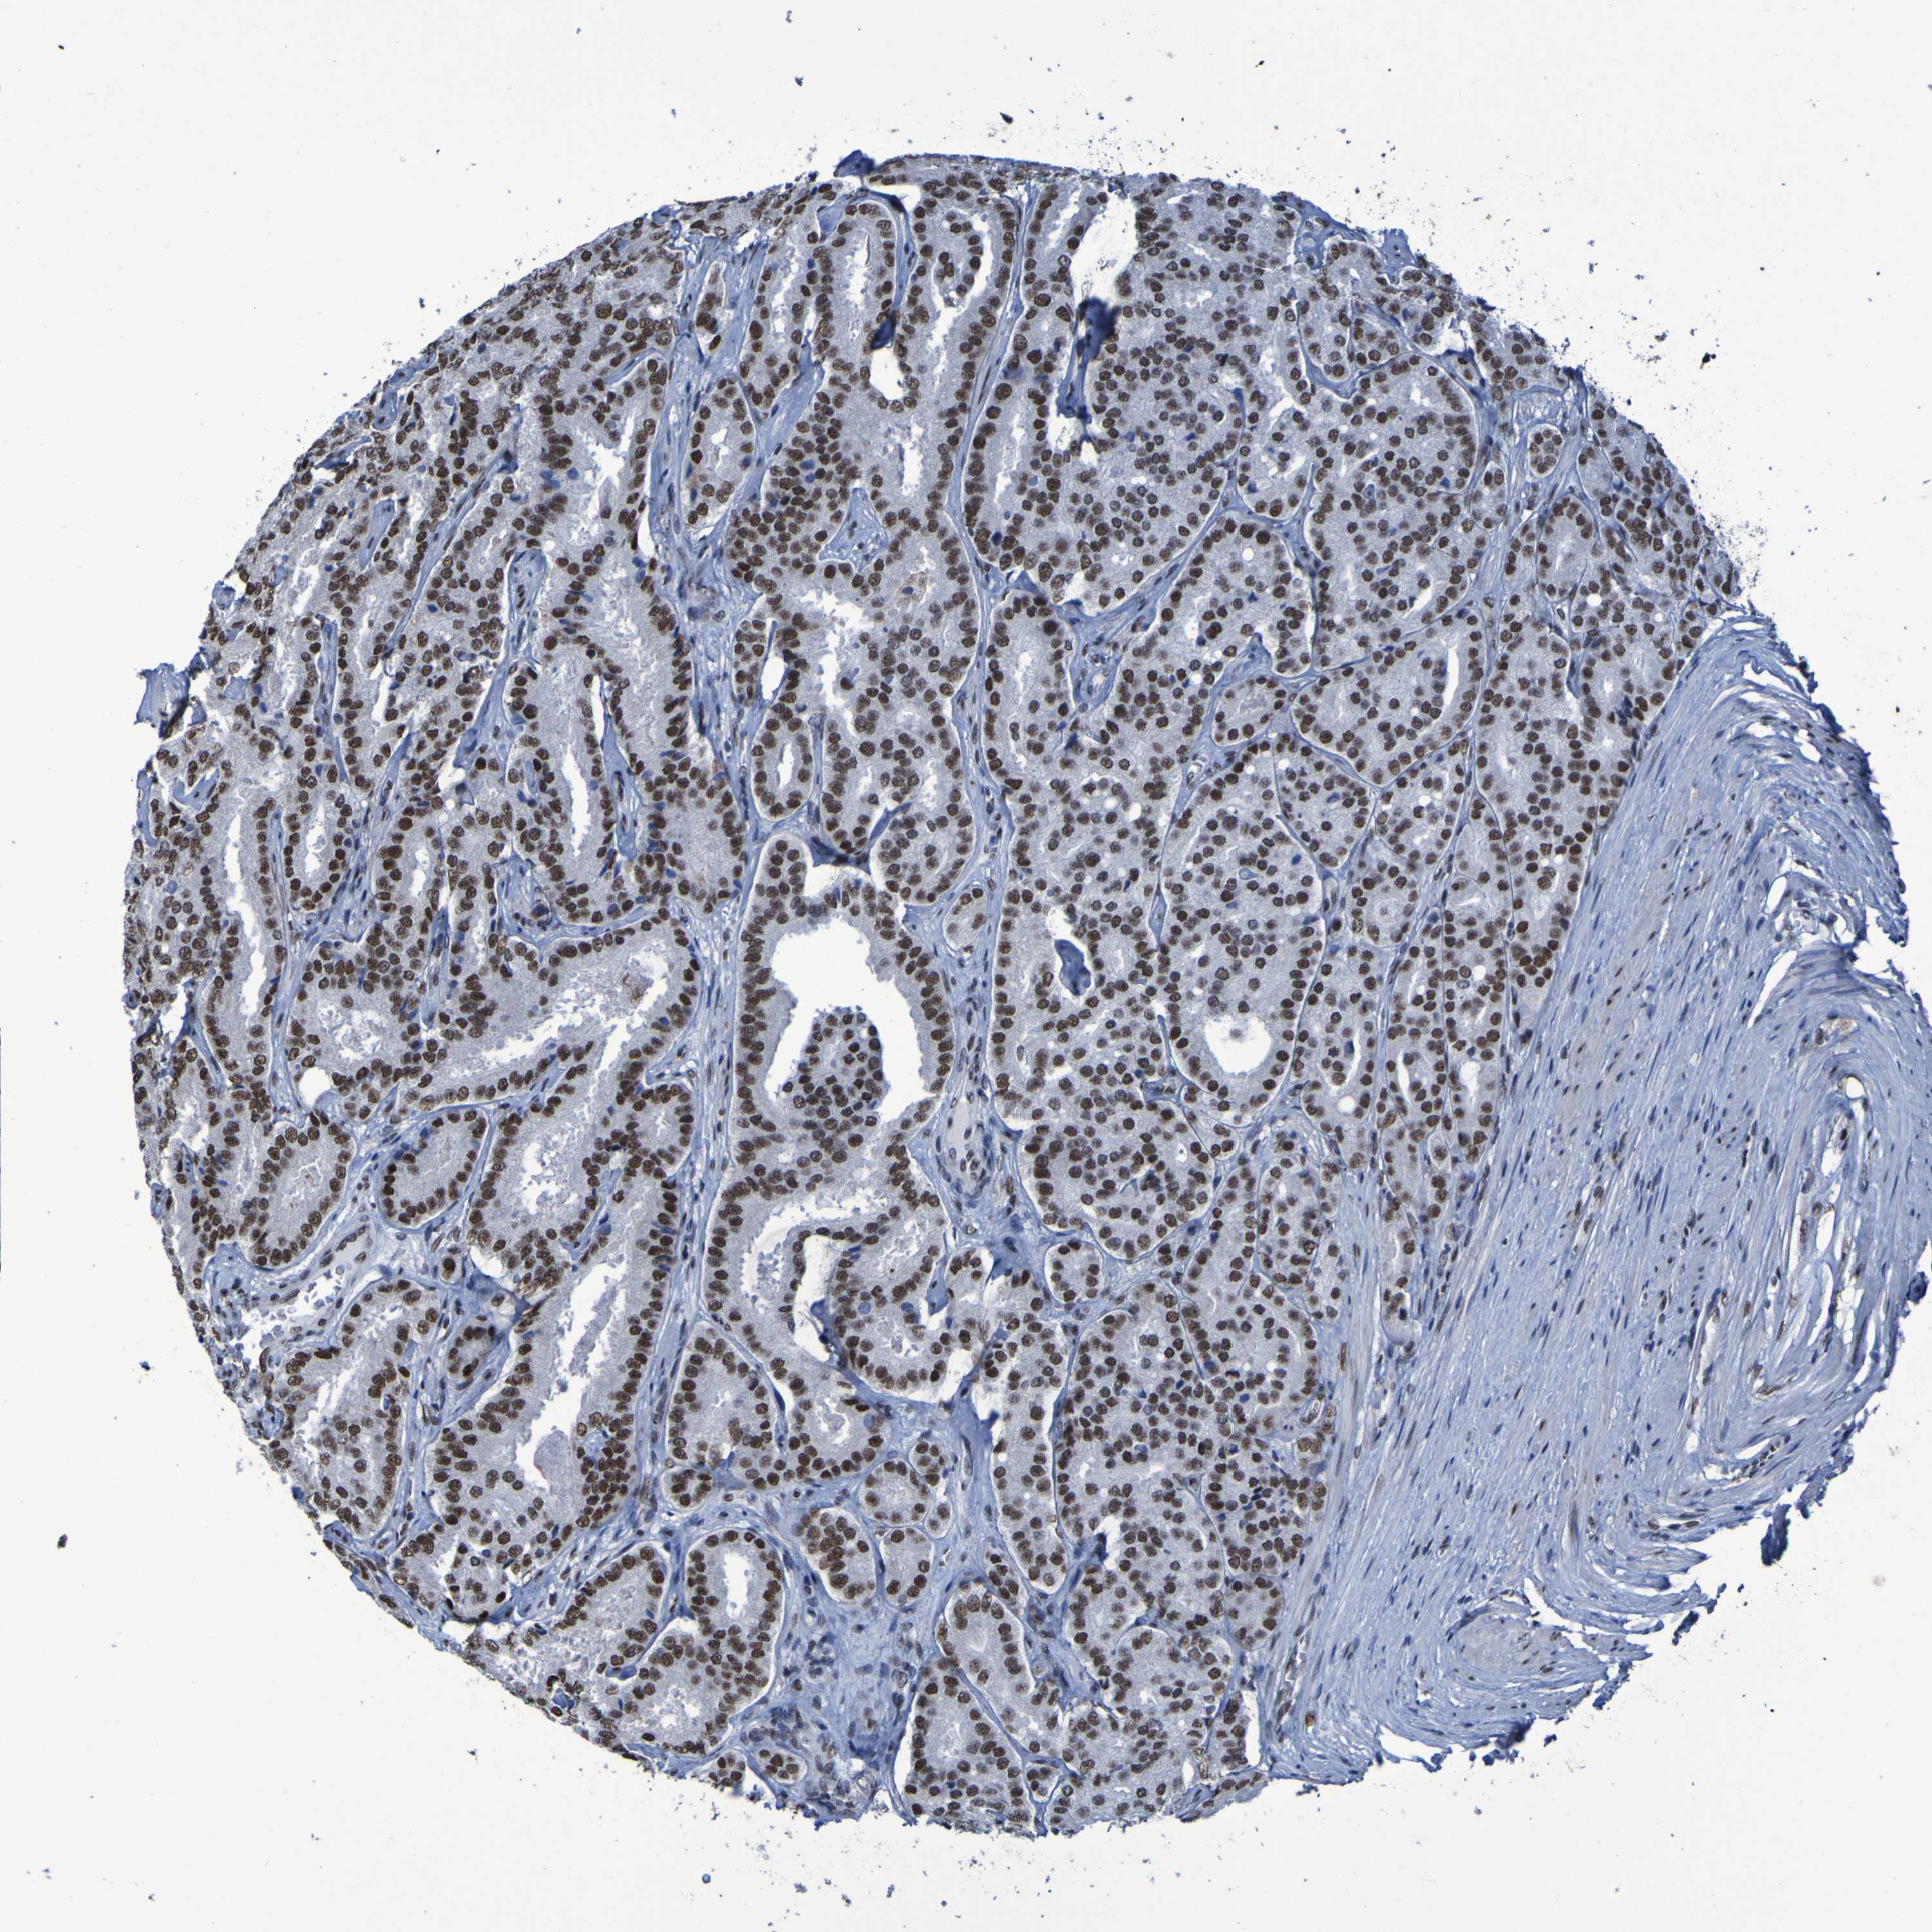

PROSTATE CANCER - Protein expressioni

A mouse-over function shows sample information and annotation data. Click on an image to view it in a full screen mode. Samples can be filtered based on level of antibody staining by selecting one or several of the following categories: high, medium, low and not detected. The assay and annotation is described here.

Antibody stainingi

Antibody staining in the annotated cell types in the current human tissue is reported as not detected, low, medium, or high, based on conventional immunohistochemistry profiling in selected tissues. This score is based on the combination of the staining intensity and fraction of stained cells.

Each image is clickable and will lead to virtual microscopy that enables deeper exploration of all samples and also displays staining intensity scores, fraction scores and subcellular localization as well as patient and tissue information for each sample.

Antibody HPA026092

Staining

High

Medium

Low

Not detected

Intensity

Strong

Moderate

Weak

Negative

Quantity

>75%

75%-25%

<25%

None

Location

Nuclear

Cytoplasmic/membranous

Cytoplasmic/membranous,nuclear

Adenocarcinoma, High grade

Adenocarcinoma, Low grade